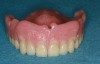

Figure 24 – Overdenture with flange to restore lip support

Figure 24

Correctly completing a treatment plan for the edentulous patient is very important. Some edentulous patients may not be candidates for fixed overdentures due to the lack of existing alveolar bone. To restore the lip support, a flange is often necessary, or an extensive amount of bone grafting must be completed. A flange cannot be attached onto a fixed bridge because the patient will not be able to clean under it (Figure 24).